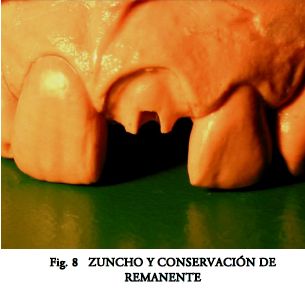

Como principios generales de su rehabilitación se incluye evaluar: a) la ecuación Remanente-Fuerzas Resultantes (2); b) la necesidad del Reforzado Cuspídeo (2, 3); y c) el de tallar 2 mm de abrazadera alrededor de todo el cuello del diente: Efecto Zuncho (4).

Actualmente existe una abrumadora presencia de trabajos que avalan su uso (7, 8, 12, 13, 14). Sin embargo en nuestro país no han desplazado de forma automática a las técnicas tradicionales. Quizás porque nuestra escuela restauradora clásica (15), basada en aleaciones coladas nobles (y conservadora al máximo de los tejidos dentarios) (Fig.7 a 10), ha obtenido un éxito predecible a lo largo de los años. Pero sus altos costos, compleja manipulación, su casi imposibilidad de remoción para retratamiento, sumado a la aparición de fracturas graves cuando falla la técnica, abren paso a nuevas alternativas que se están adoptando con la debida prudencia.

- Fabricación del Muñón Coronario.- Esta etapa tan fácilmente resuelta por los colados, siempre es problemática en los prefabricados. En casos de discrepancia entre los ejes coronario y radicular (Fig.7) puede ser necesario cambiar de sistema (Figs. 8, 9, 10).